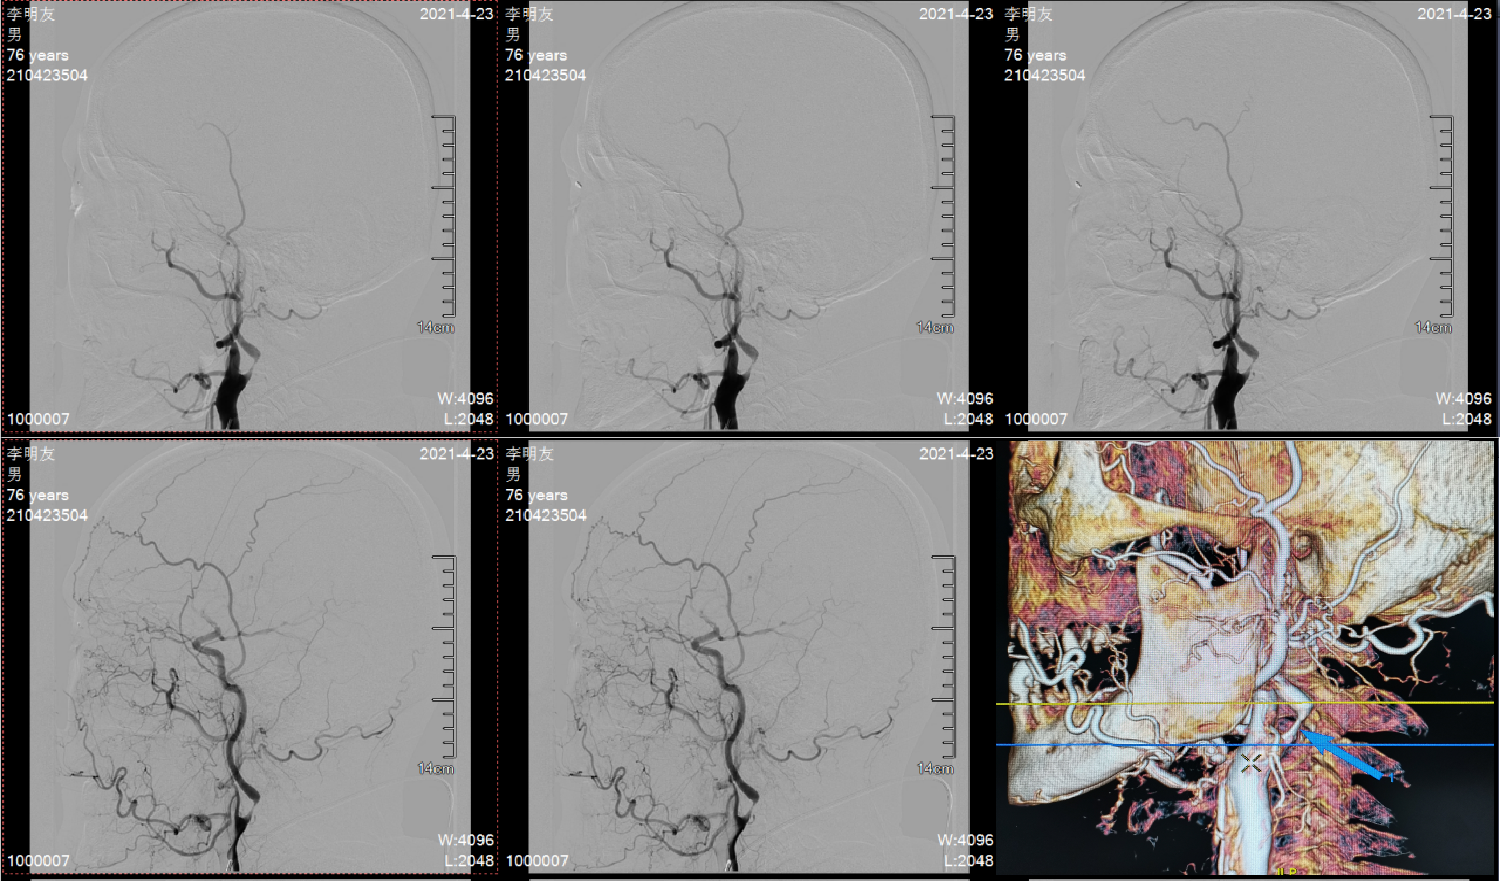

造影显示左侧颈内动脉重度狭窄,远端血流缓慢;狭窄部位在颈2、3椎体水平